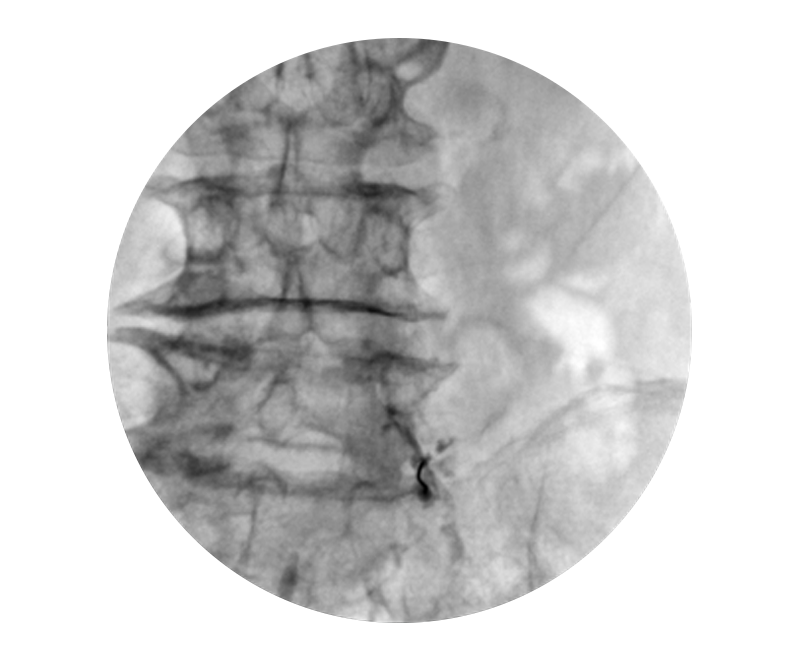

À̵¿½Ä X-ray ÃÔ¿µ ±â°è¸¦ ÀÌ¿ëÇÏ¿© ½Ã¼ú ºÎÀ§ÀÇ ÃÔ¿µÀ» ÅëÇØ ¹Ù´ÃÀ̳ª

ÁÖ»çÀÇ ¾à¹°À» ½Å°æºÐÀý ºÎÀ§¿¡ ÁÖÀÔÇÏ´Â ½Ã¼ú·Î Àϸí '½Å°æÂ÷´Ü¼ú'À̶ó ºÒ¸³´Ï´Ù.